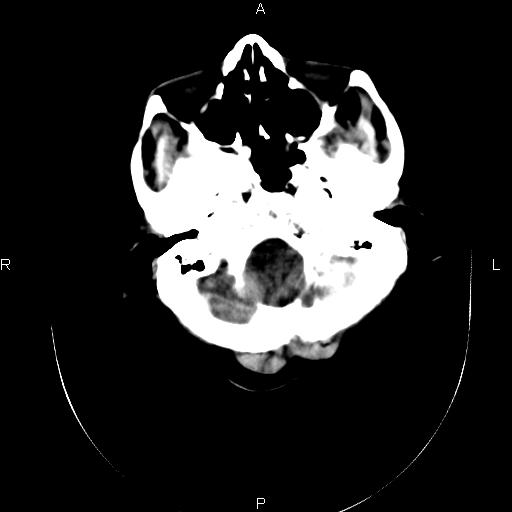

标题: CT20052:女76岁既往偶有头疼。

近三天来阵发性头剧疼 头晕加重。考虑蛛血?双额叶颅板下低密度是否为蛛网膜囊肿?请老师们指教指教!

1、蛛网膜下腔出血;

2、脑萎缩,双额叶颅板下低密度为增宽的蛛网膜下腔。

2、双侧额部硬膜下积液;

3、轻度脑积水(三脑室球形扩大),扩大的侧脑室颞角和前角都有张力。

1)蛛网膜下腔出血。2)双侧侧脑室少量出血。3)双侧额部硬膜下积液。4)脑积水。

1、蛛网膜下腔出血。

2、双侧额骨颅骨内板下的带状低密度影,不是增宽的蛛网膜下腔。依据:本病人本身有蛛网膜下腔出血,双侧额叶表面有一带状高密度影,那才是有出血的蛛网膜下腔。前面的带状低密度影(额骨内板下)是硬膜下积液表现,其内没有出血迹象,与出血的蛛网膜下腔界限清晰。